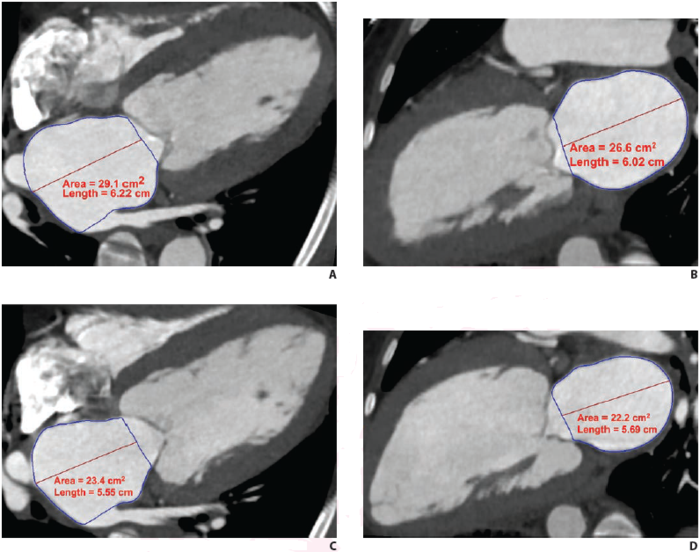

LAVmax (A and B), LAVmin (C and D), and LAEF Using Cardiac CTA

image: LAEF was calculated as (LAVmax-LAVmin)/LAVmax x 100. Given LAVmax of 109 mL and LAVmin of 80 mL,LAEF was calculated to be 27%. view more